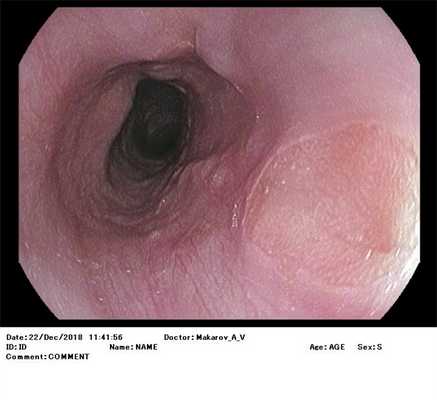

Пациентке выполнялась резекция слизистой пищевода в нижней трети. При эндоскопическом исследовании обнаружена рубцовая деформация просвета пищевода, проходимая для среднекалиберного аппарата.

"кошачий пищевод" "трахеизация" пищевода. Из анамнеза: стойкая дисфагия и диспепсия. Пациент из кардиологии. Находка случайная.